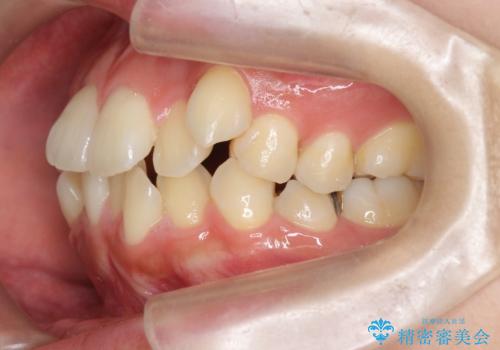

八重歯を矯正治療で治したい!

- 八重歯・がたつきのある歯並びの改善を求めて来院されました。

全部の歯が入り切るスペースがなかったため、小臼歯4本を抜去しワイヤーを用いたマルチブラケット矯正を選択しました。